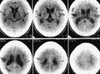

Эти данные подтверждаются результатами сканирования мозга, которые показали, что у пациентов, получавших алемтузумаб, мозг увеличился в размерах, в то время как у остальных - стал меньше. А это означает, что алемтузумаб позволяет восстановить поврежденные ткани мозга.